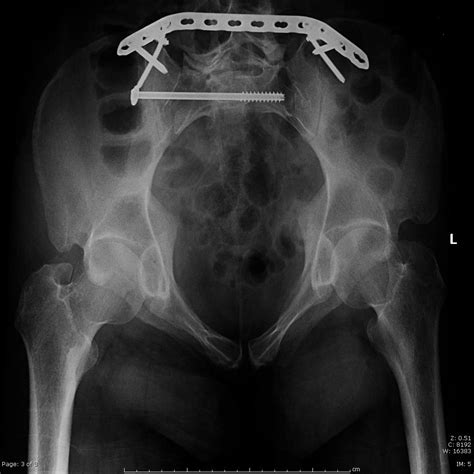

• Sacral Screw Fixation: A minimally invasive technique where screws are placed under fluoroscopic guidance to bridge the fracture site.

• Sacral Plate Fixation: Used for more complex or multi-fragment fractures to provide rigid internal stabilization.